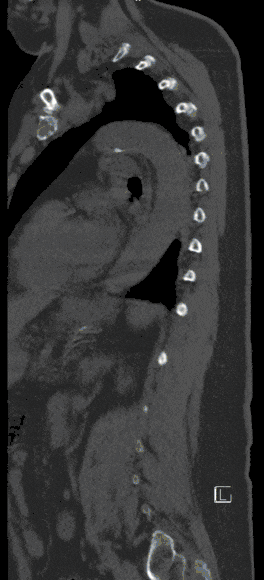

Vertebral Fractures

Vertebral body fractures are treated in-house in close interdisciplinary cooperation with the University Department of Trauma Surgery.

Injuries to the spine can lead to damage to the spinal cord and nerves, ranging from mild neurological disorders to paraplegic syndromes.